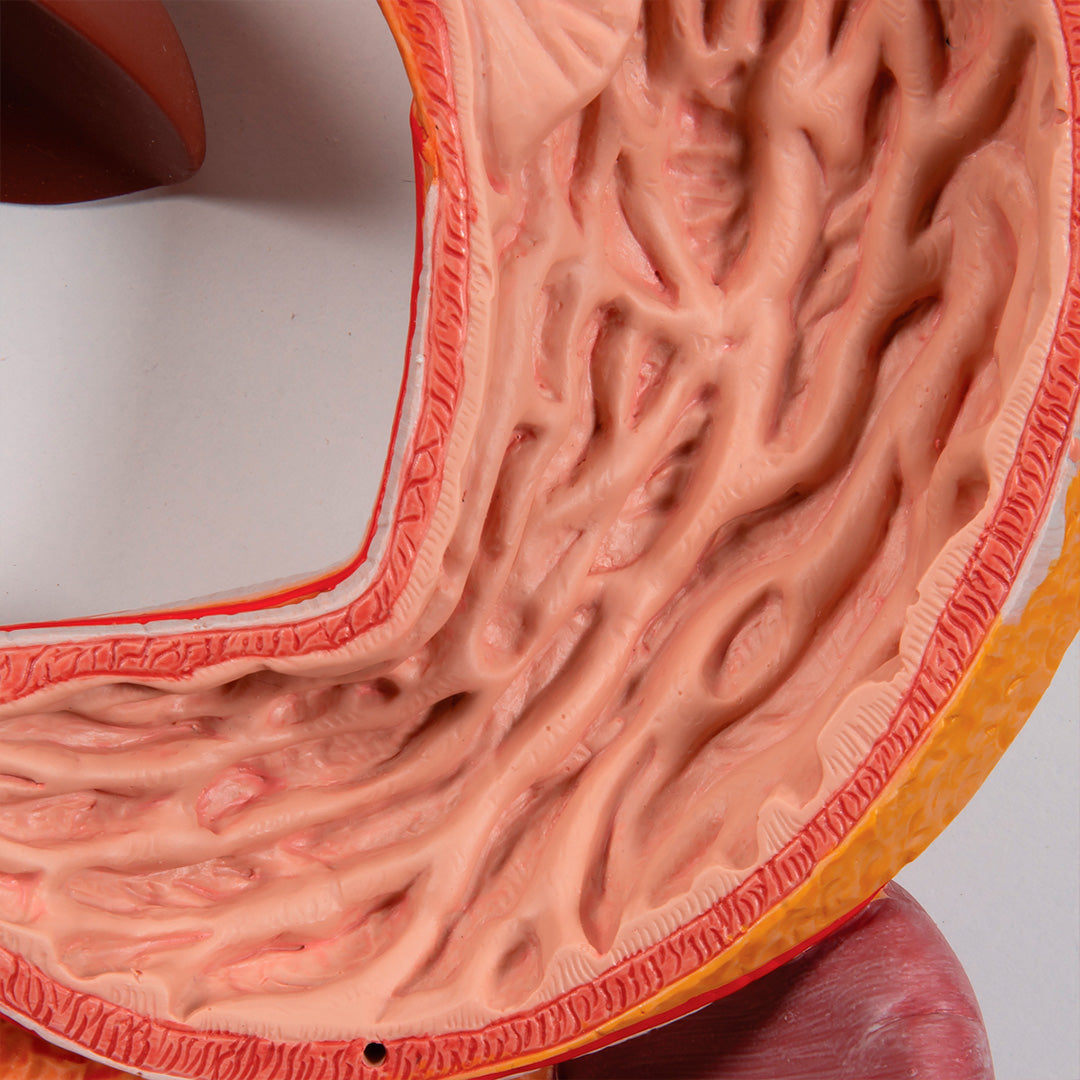

• Tracto gastro-intestinal

El colón transversal y la pared delantera del estómago se pueden desmontar.